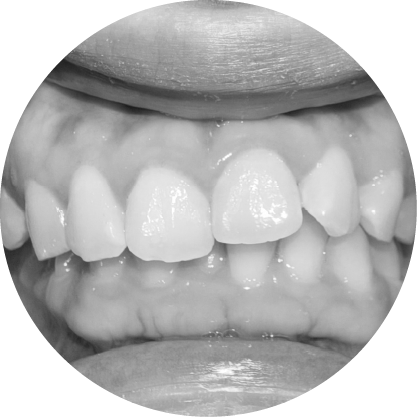

ประเภททั่วไปของ ความผิดปกติของการสบฟัน

Overbite teeth illustration – upper teeth overlap lower

ฟันหน้ายื่น (ฟันสบลึก)

แก้ไขฟันสบลึก เพื่อรอยยิ้มที่สมดุล

ฟันสบลึกเกิดขึ้นเมื่อฟันบนยื่นทับฟันล่างมากเกินไป หากปล่อยไว้โดยไม่รักษา อาจส่งผลต่อรูปลักษณ์และสุขภาพช่องปาก การรักษาทางทันตกรรมจัดฟันมีเป้าหมายเพื่อฟื้นฟูความสมดุลและการทำงานของฟัน เพื่อให้คุณมีรอยยิ้มที่มั่นใจ

ตัวอย่างในชีวิตจริง